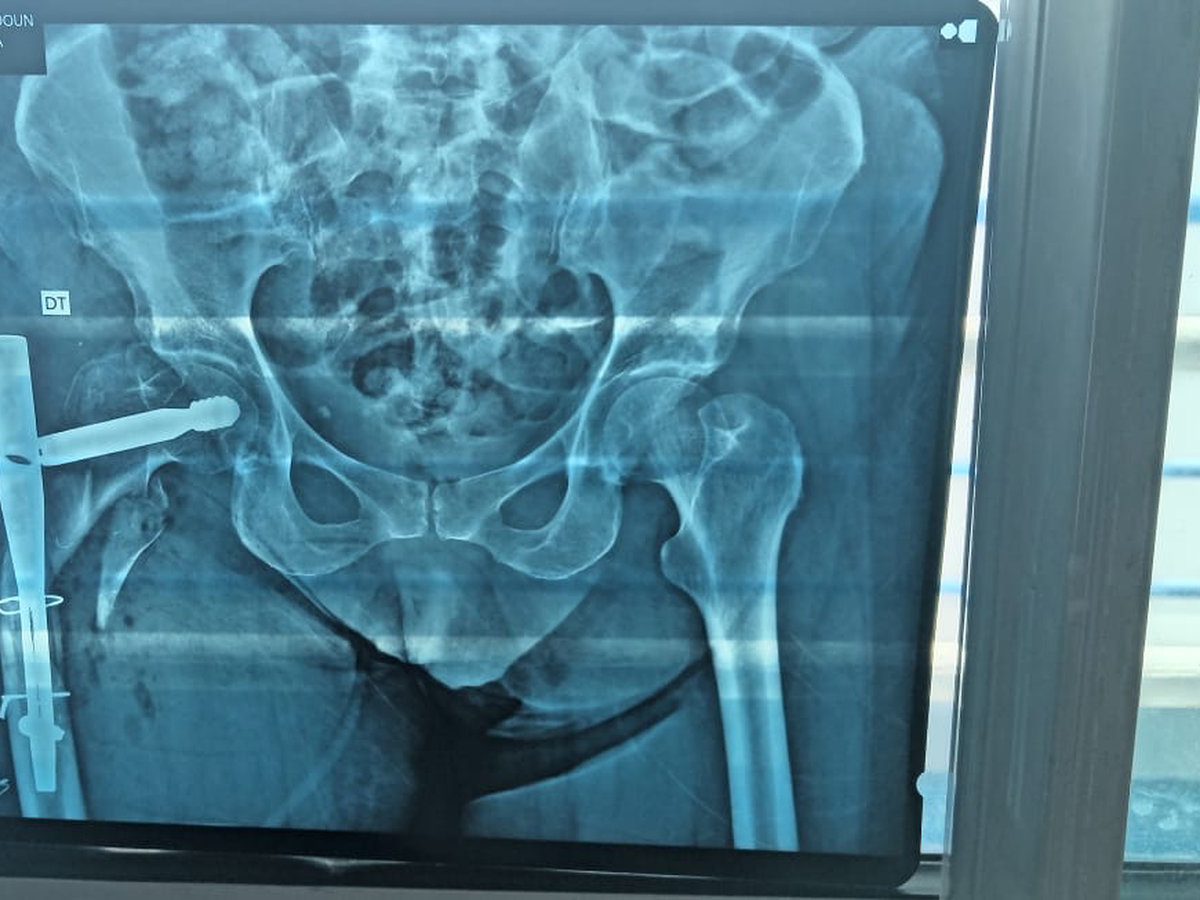

Je m’appelle Imane je vis à Montréal. Ma maman risque l’amputation après un grave accident le 22 juillet au Maroc.

Six opérations ont échoué. Seule une clinique spécialisée peut sauver sa jambe — mais nous n’avons pas les moyens.

My name is Imane living in Montreal. My mom is fighting to keep her leg after a terrible car accident on July 22nd in Morocco.

Six surgeries failed. Doctors say only a specialized clinic can save her from amputation — but it’s far beyond our means.